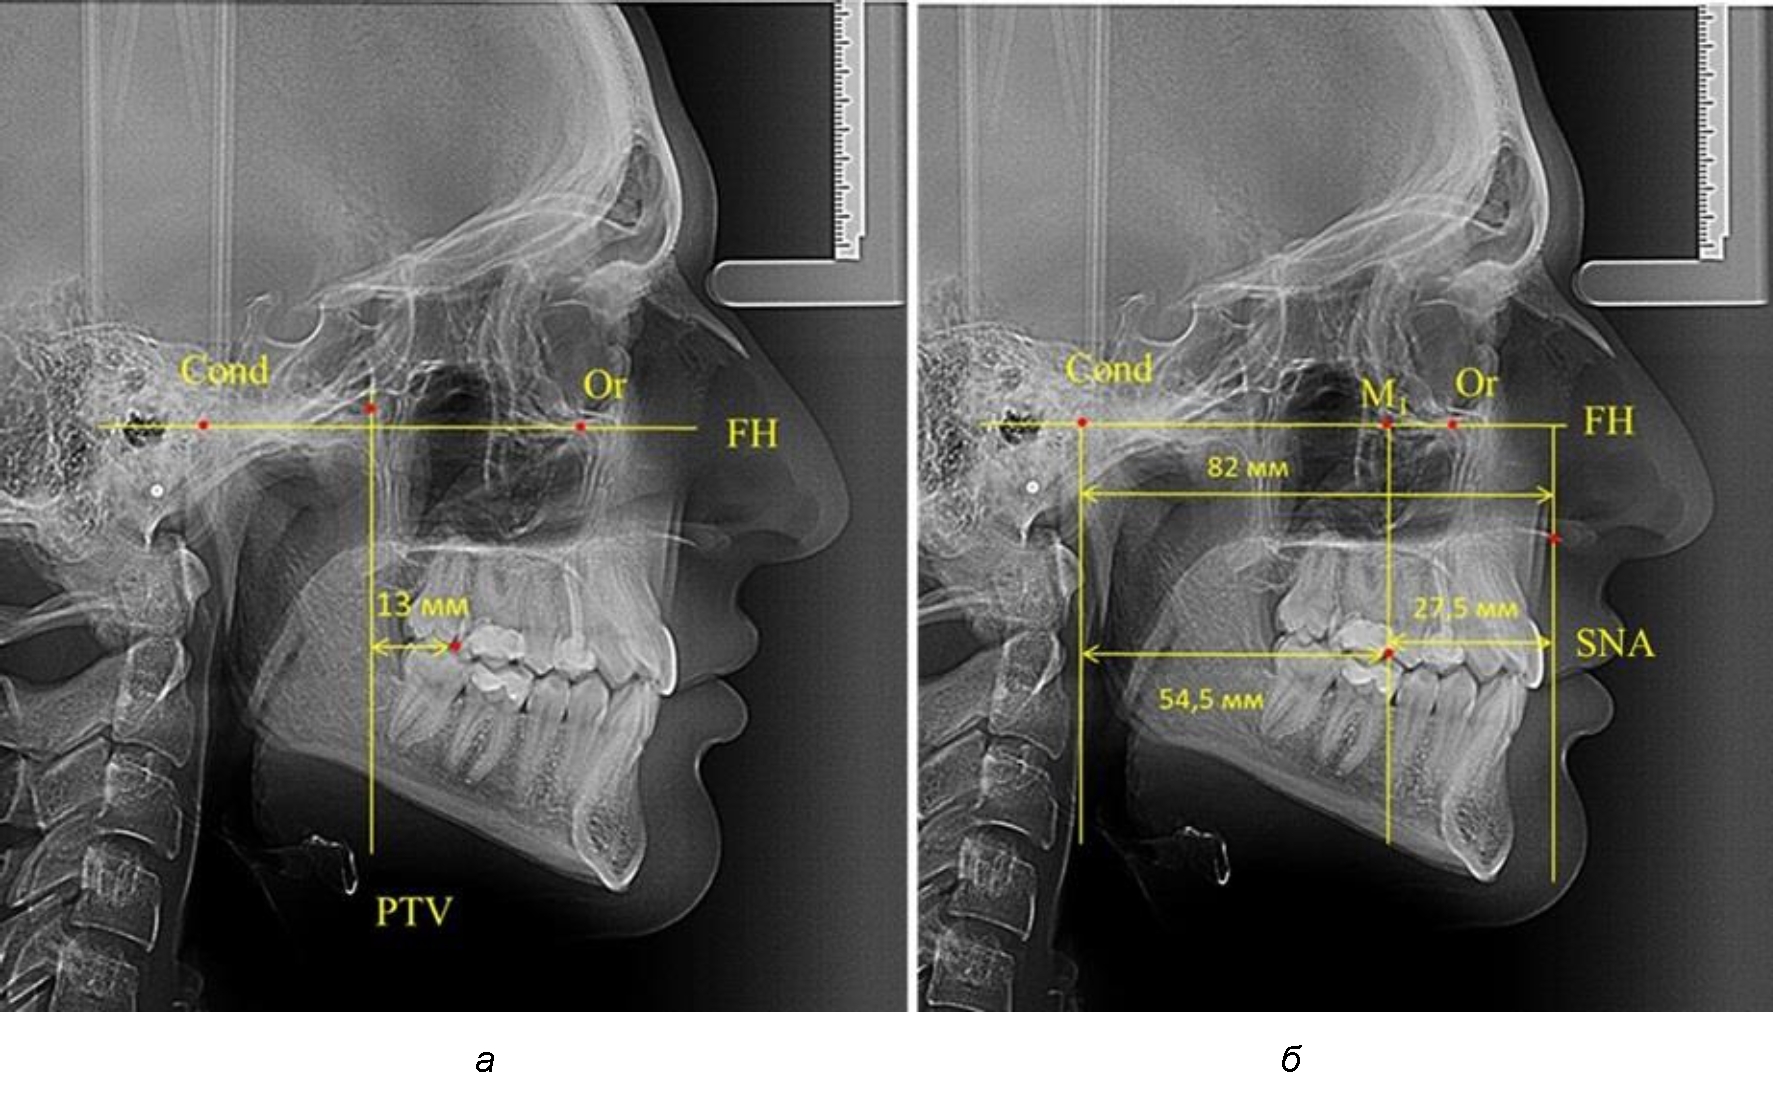

В то же время при увеличенном расстоянии от крыловидной вертикальной плоскости PTV до дистальной поверхности верхнего первого постоянного моляра, равное 23 мм, сагиттальный размер гнатического отдела составил 92 мм. При этом отношение кондилярно-спинального расстояния к кондилярно-молярному размеру (30,5), так же, как и при малых размерах, было близким к коэффициенту 1,5, что представлено на рис. 3.

Рис. 3. Особенности положения первых моляров по R. E. McDonald (а) и по предложенному методу (б) при увеличенном молярно-крыловидном расстоянии